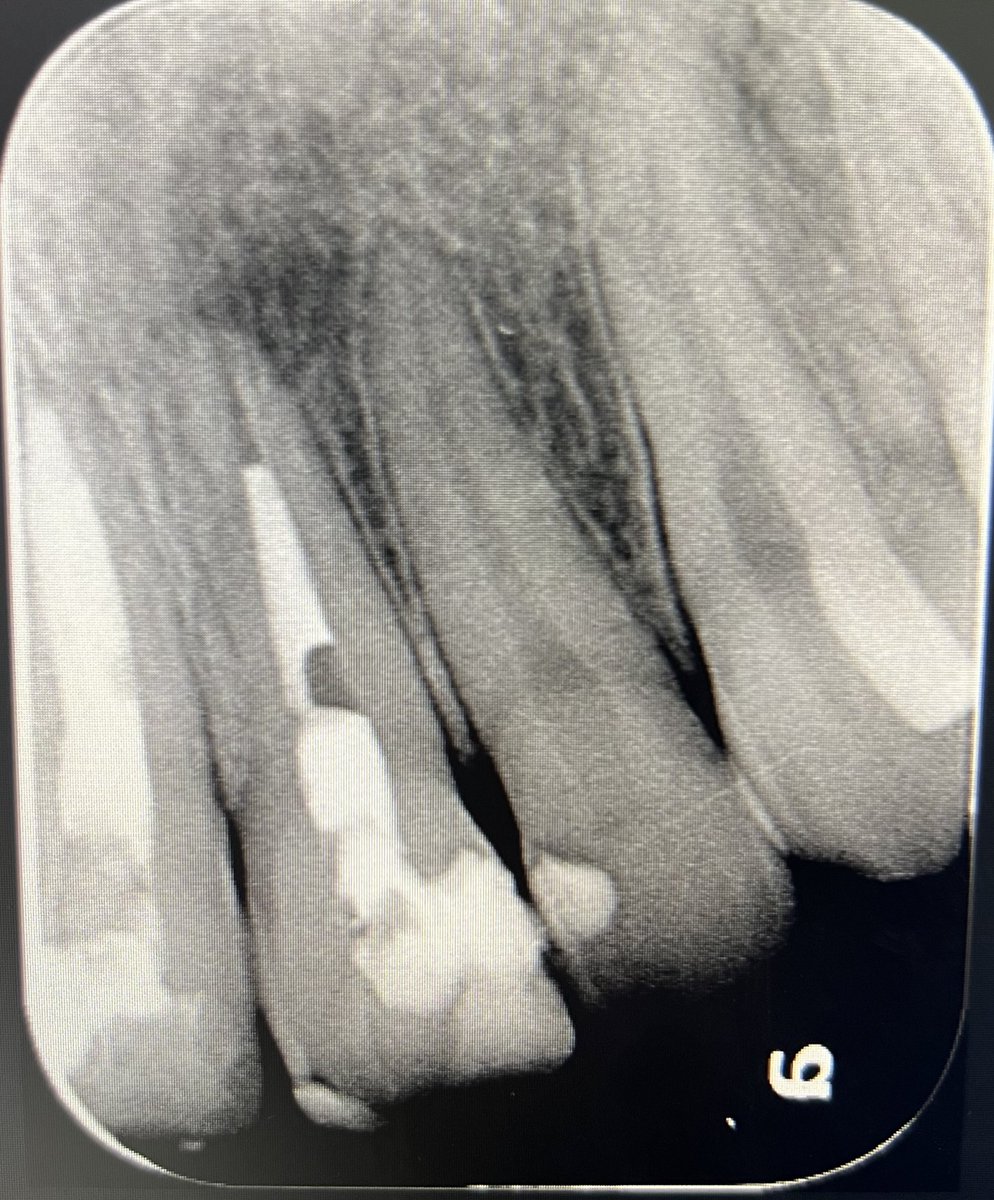

Today’s case:

Rct of #11 Dx : PI/AAA

• 1st visit: Open access, irrigation, abscess drainage, and dressing the canal with Ca(OH)₂.

• 2nd visit (after 30 days): Reopening the tooth, irrigation performed; the canal was completely dry and ready for obturation.

Patient is fine😁